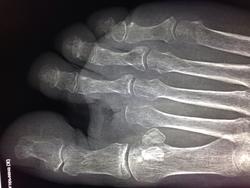

Здравствуйте! Больная 54 г. Сахарный диабет. Ампутация фаланг 2-го пальца левой стопы. Снимок сделан на предмет деструкции. Поделитесь пожалуйста своим мнением по этому поводу!

Деструкция головки 5-й плюсневой кости.

Спасибо Вадим! А как вы считаете, нет ли деструкции головки 1-ой плюсневой кости!

сомнительная деструкция, больше на остеопороз похож

Нет деструкции.

Лично меня смутила первая плюсневая кость, точнее ее головка... Ваше мнение, что там нет деструкции?

Обычно подобного рода пациентов можно встретить в отделении гнойной хирургии. Хирурги ориентируются не только рентгеновской картиной- больше расположением гнойных затеков, свищевых ходов.Если бы при подобной картине я написал в заключении только остеопороз в нашей больнице хирурги меня бы не поняли. Самое главное, что подобного рода процесс движется в одну сторону.К сожалению пальцев со временем становится меньше.

Я вас понял Вадим. Думаю, что ко мне завтра хирург придет с претензиями, так как я по неопытности в заключение вынес только остеопороз.

Завтра хирурги будут тыкать пальцами в любое из указанных мест и кричать, что рентгенолог не видит деструкции, а у пациента  свищ и будут демонстрировать лоток с гноем.

На будущее: при диабетических стопах делайте снимки обеих стоп, и уточняйте наличие/отсутсвие свищей на стороне поражения; легче будет.

Еще раз о былом, обходились без амб.карт - спрашивали.... А, по данным снимкам за 5 мин. любому хирургу докажу, что нет деструкции,  за 2 мин., что есть деструкция. smiley НЕ абсолютизируйте изображения( кому-то видно и все ясно, кому-то нет) Скорее и там, и там есть( косвенные изменения прилежащих мягких тканей, но это не аксиома.)

Не зная анамнеза, чисто по снимкам, деструкцию не указал бы. Но, учитывая клинику, м.б.